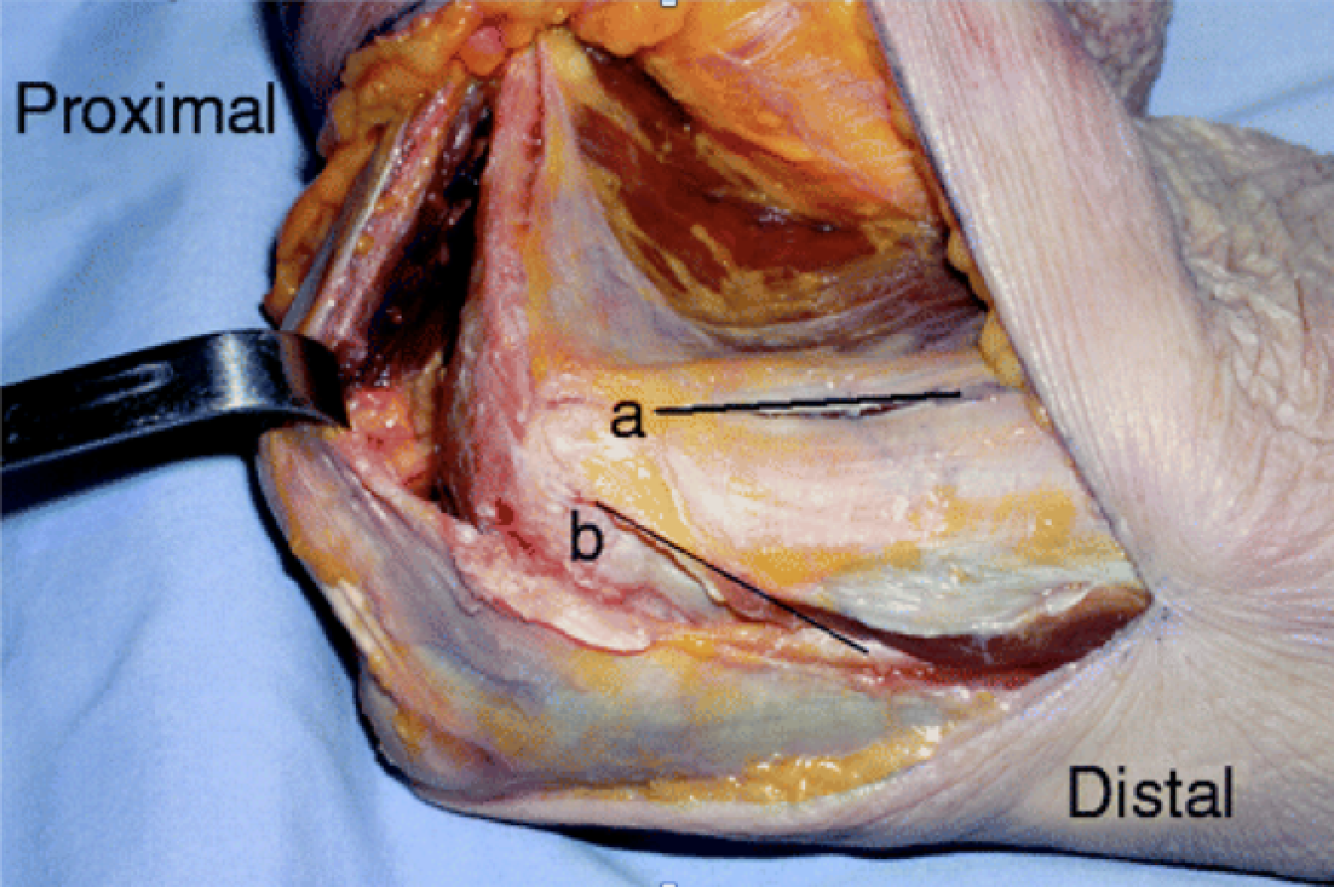

Hotchkiss Medial Over-the-top

Interval:

- Proximally: Intermuscular septum between triceps (radial n.) & brachialis (radial n, median n.)

- Distally: Through flexor pronator mass. FCU (ulnar n.) & FDS/Palmaris Longus (Median n.)

Approach: Unroof, identify and mobilize the ulnar n. Split flexor pronator mass, and elevate anteriorly. Care to be taken for MUCL

Dangers: Ulnar N. MUCL, Median N. Brachial A., MABCN (found on fascia anterior to septum)

FCU Split

Interval: None, between two heads of FCU (Ulnar N.)

Approach: Identify, unroof and protect median n. Split two heads of FCU and elevate anteriorly. Care to be taken not to injure MUCL

Dangers: MUCL, Ulnar N. Median N. Brachial A.

Modified Taylor and Scham

Interval: ECU (PIN), FCU (Ulnar N.)

Approach: Dissect down to subcutaneous boarder of ulan and lift everything anteriorly. Akin to the boyd but on the medial side. Gives access to base of coranoid/sublime tubercle

Dangers: Ulnar N., MUCL

*1 = Hotchkiss, 2= FCU Split, 3=Taylor Scham